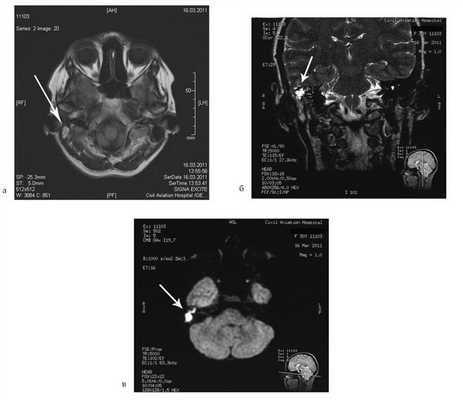

Таким образом, можно было сделать вывод, что значительное увеличение ганглиоцитомы произошло в пубертатный период. По поводу клинических и рентгенологических признаков окклюзионной гидроцефалии с перивентрикулярным отеком больной произведено вентрикулоперитонеальное шунтирование. После разрешения гидроцефалии у пациентки сохранялось опущение миндаликов мозжечка в большое затылочное отверстие (рис. 6, 7), в связи с чем была выполнена декомпрессия краниовертебрального перехода и биопсия образования мозжечка (рис. 8).

Рис. 6. КТ головного мозга после ликворошунтирующей операции. Рис. 7. МРТ после ликворошунтирующей операции. Определяется ганглиоцитома правого полушария мозжечка с вклинением правой миндалины в большое затылочное отверстие, компрессией и смещением прилежащих анатомических структур. Рис. 8. УЗ-изображение ганглиоцитомы при проведении биопсии. Определяется гиперэхогенное образование с нечеткими контурами.

В дальнейшем проведено генетическое и морфологическое исследование, которое подтвердило наличие мутации гена PTEN в хромосоме 10q23.31, что верифицировало болезнь Лермитта—Дюкло и исключило другие синдромы.